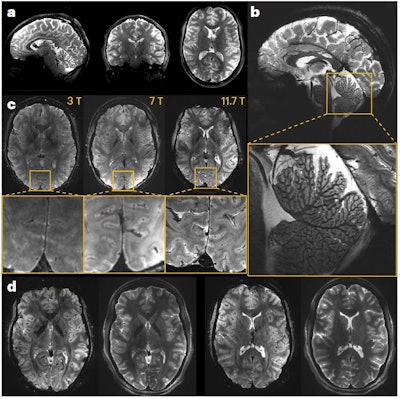

In vivo images of the human brain obtained at 11.7T. (A) In vivo 3D T2 variable flip angle turbo spin-echo acquisition at 11.7T with parallel transmission GRAPE universal pulses (resolution 0.55 × 0.55 × 0.55 mm3, acquisition time 13 min) demonstrating the high B1+ (RF) field homogeneity reached throughout the whole brain volume. (B) In vivo T2*-weighted 2D GRE sagittal slice (resolution 0.2 × 0.2 × 1 mm3, acquisition time 8 min 30 s). (C) T2* weighted 2D GRE axial images acquired at 3T (left), 7T (middle) and 11.7T (right) with identical acquisition times (4 min 17 s), while keeping similar contrast-to-noise ratio through adjusted acquisition parameters (FA (°), TR (ms) and TE (ms) of 27, 750 and 45; 34, 950 and 25; 27, 600 and 20 at 3, 7 and 11.7T, respectively) and spatial resolution (0.5, 0.325 and 0.2-mm in-plane resolution for 3, 7 and 11.7T, respectively, 1-mm thickness). (D) The 11.7T T2*-weighted 2D GRE axial images (resolution 0.19 × 0.19 × 1 mm3, acquisition time 5 min 16 s) juxtaposed to turbo spin-echo T2-weighted images (resolution 0.3 × 0.3 × 1 mm3, acquisition time 4 min 26 s). All figures courtesy of Nicolas Boulant, PhD, et al and Nature Methods.

First author Nicolas Boulant, PhD, head of the Iseult Project and director of research at the CEA, and colleagues were also satisfied with the quality of the images acquired on the first volunteers, which exceeded the team's most optimistic expectations, the authors noted in the media. They acquired structural in vivo images of the human brain with a high resolution down to 0.19 x 0.19 x 1 mm3 in around five minutes and with good signal uniformity without serious artifacts of RF field inhomogeneity. Furthermore, these images indicated sufficient SNR to boost spatial resolution further, they added.